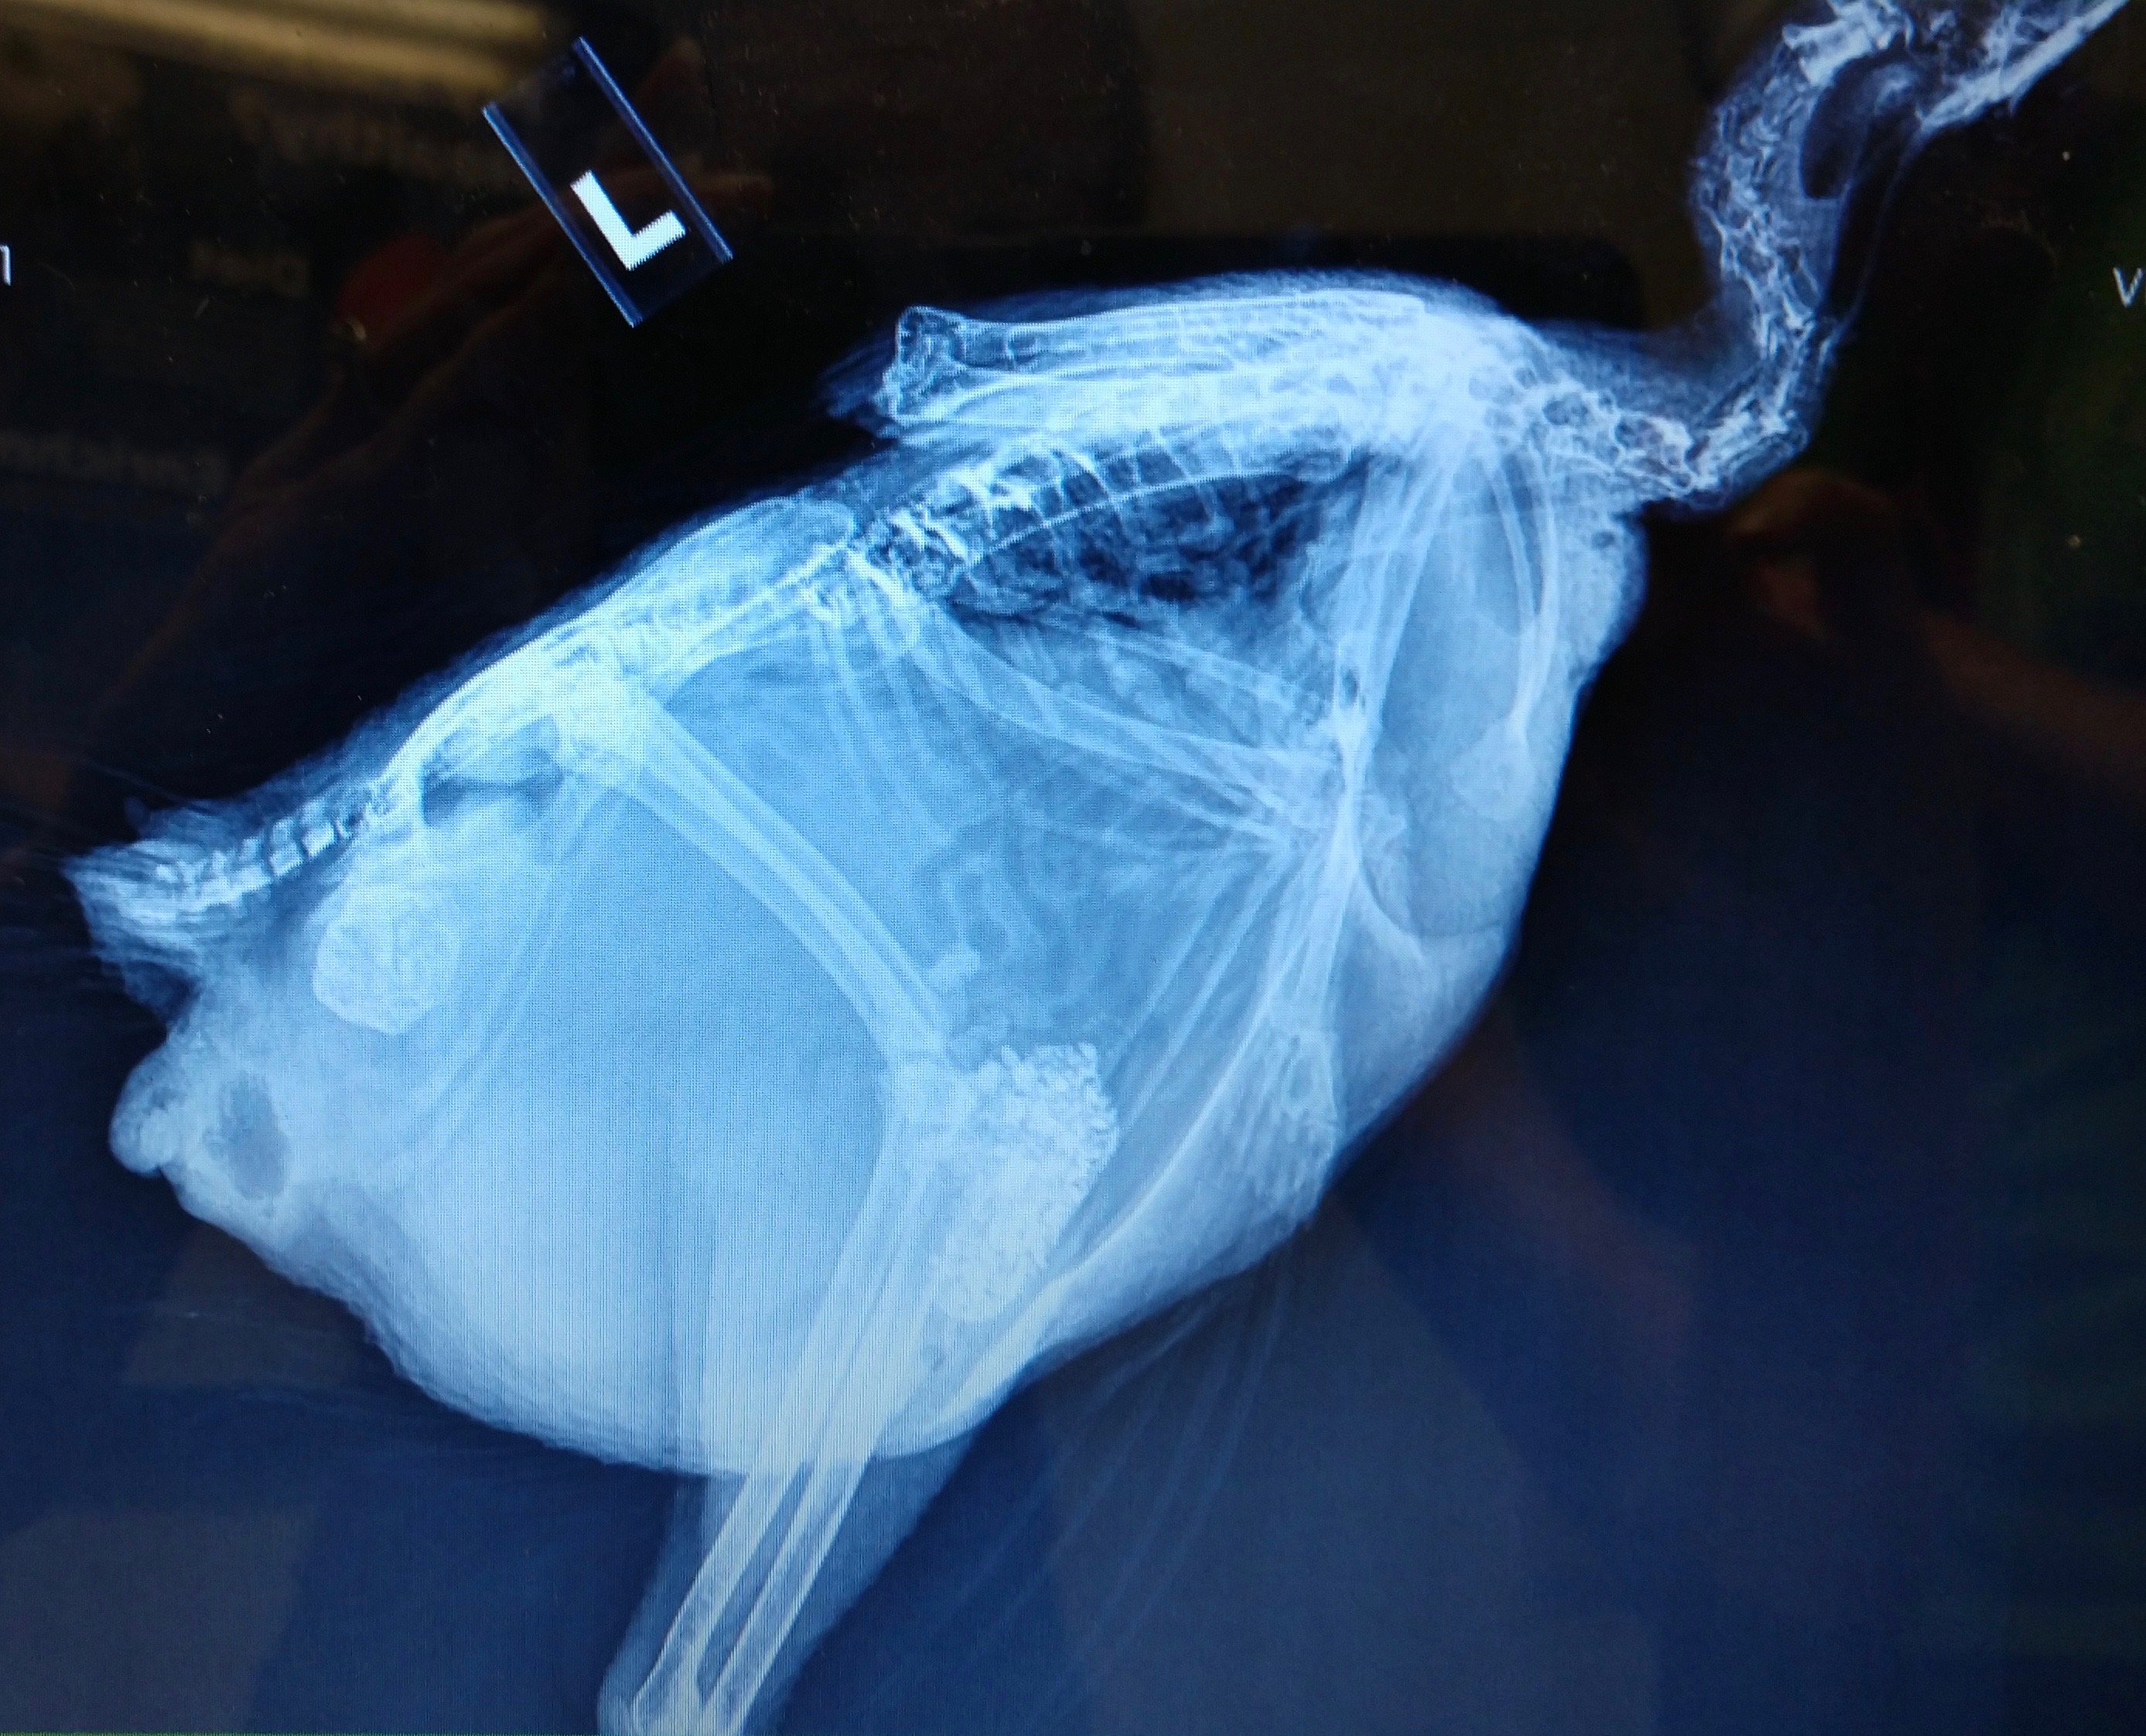

You’ll note that in some of the x-rays you can see a mass that looks like a ball of crumpled aluminum foil in her oviduct region. Those images are from the first visit, the ones with it missing are after she passed that obstruction. The mass itself is what’s in the Ziploc bag, both intact and after the vet broke it apart to examine contents. I wish we could have gotten a cross-section image, but at the time I felt it might be important for the vet to see exactly how it came out and cross reference to confirm nothing appeared to have been left behind.

Can you spot something important that our vet overlooked? We still haven’t been able to get a very clear picture of what’s going on apart from that blockage, but suspect something is, just based on the continuing digestive issues and apparent fluid still present at the second x-ray. I feel like she’s laying internally periodically and reabsorbing fluid between. Outwardly, she is acting like her system is on and functioning, but nothing comes of her efforts, so that has me concerned that she is doing something and it’s just not making it’s way out. I imagine septic EYP can be ruled out, as I don’t think we would be seeing these rebounds of full energy/appetite if anything had gone septic. She has good and bad days, and the bad ones always go hand-in-hand with the watery poop. She’s definitely got us scratching our heads.

Dr Bowes: The vet did a great job of the x-rays. They indicate the ureters are full of crates, a sign of dehydration, the intestines look normal, there is a lot of internal fat. The mass is a collection of debris from the oviduct. It is crumbly and friable, the result of a hemorrhagic component. The intestines appear to be bunched up. There is something obstructing the full view of the abdomen. Is that fat or yolk peritonitis?